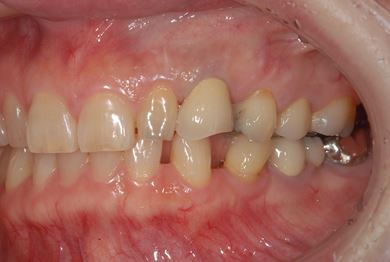

インプラントの症例写真 IMPLANT

インプラント治療

| 性別/年齢 | / 49歳 | ||||||||||||||||||||||||||||||||

| 主訴 | 乳歯がぐらついている。 | ||||||||||||||||||||||||||||||||

| 治療方針 | インプラント治療にて、機能的・審美的回復を行う。 | ||||||||||||||||||||||||||||||||

| 治療内容 | インプラント1本、メタルボンドセラミッククラウン1本 | ||||||||||||||||||||||||||||||||

| 総治療費 | 377,055円 | ||||||||||||||||||||||||||||||||

| 治療期間 | 4ヶ月 |